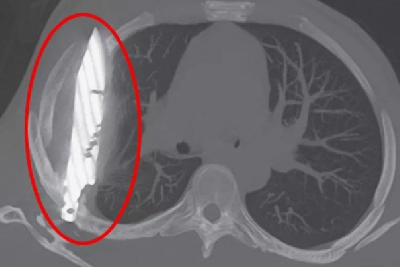

В Танзании мужчина восемь лет жил с ножом в груди

К врачам он пришел, когда из-под его соска стал подтекать гной. Его жизненные показатели были в норме, других симптомов не было. Медики увидели большое лезвие ножа только на рентгеновских снимках. Клинок прошел сквозь правую лопатку, не повредив органы.

По словам пациента, почти десять лет назад он получил множественные ранения во время ожесточенной драки, в том числе порезы на лице и туловище.